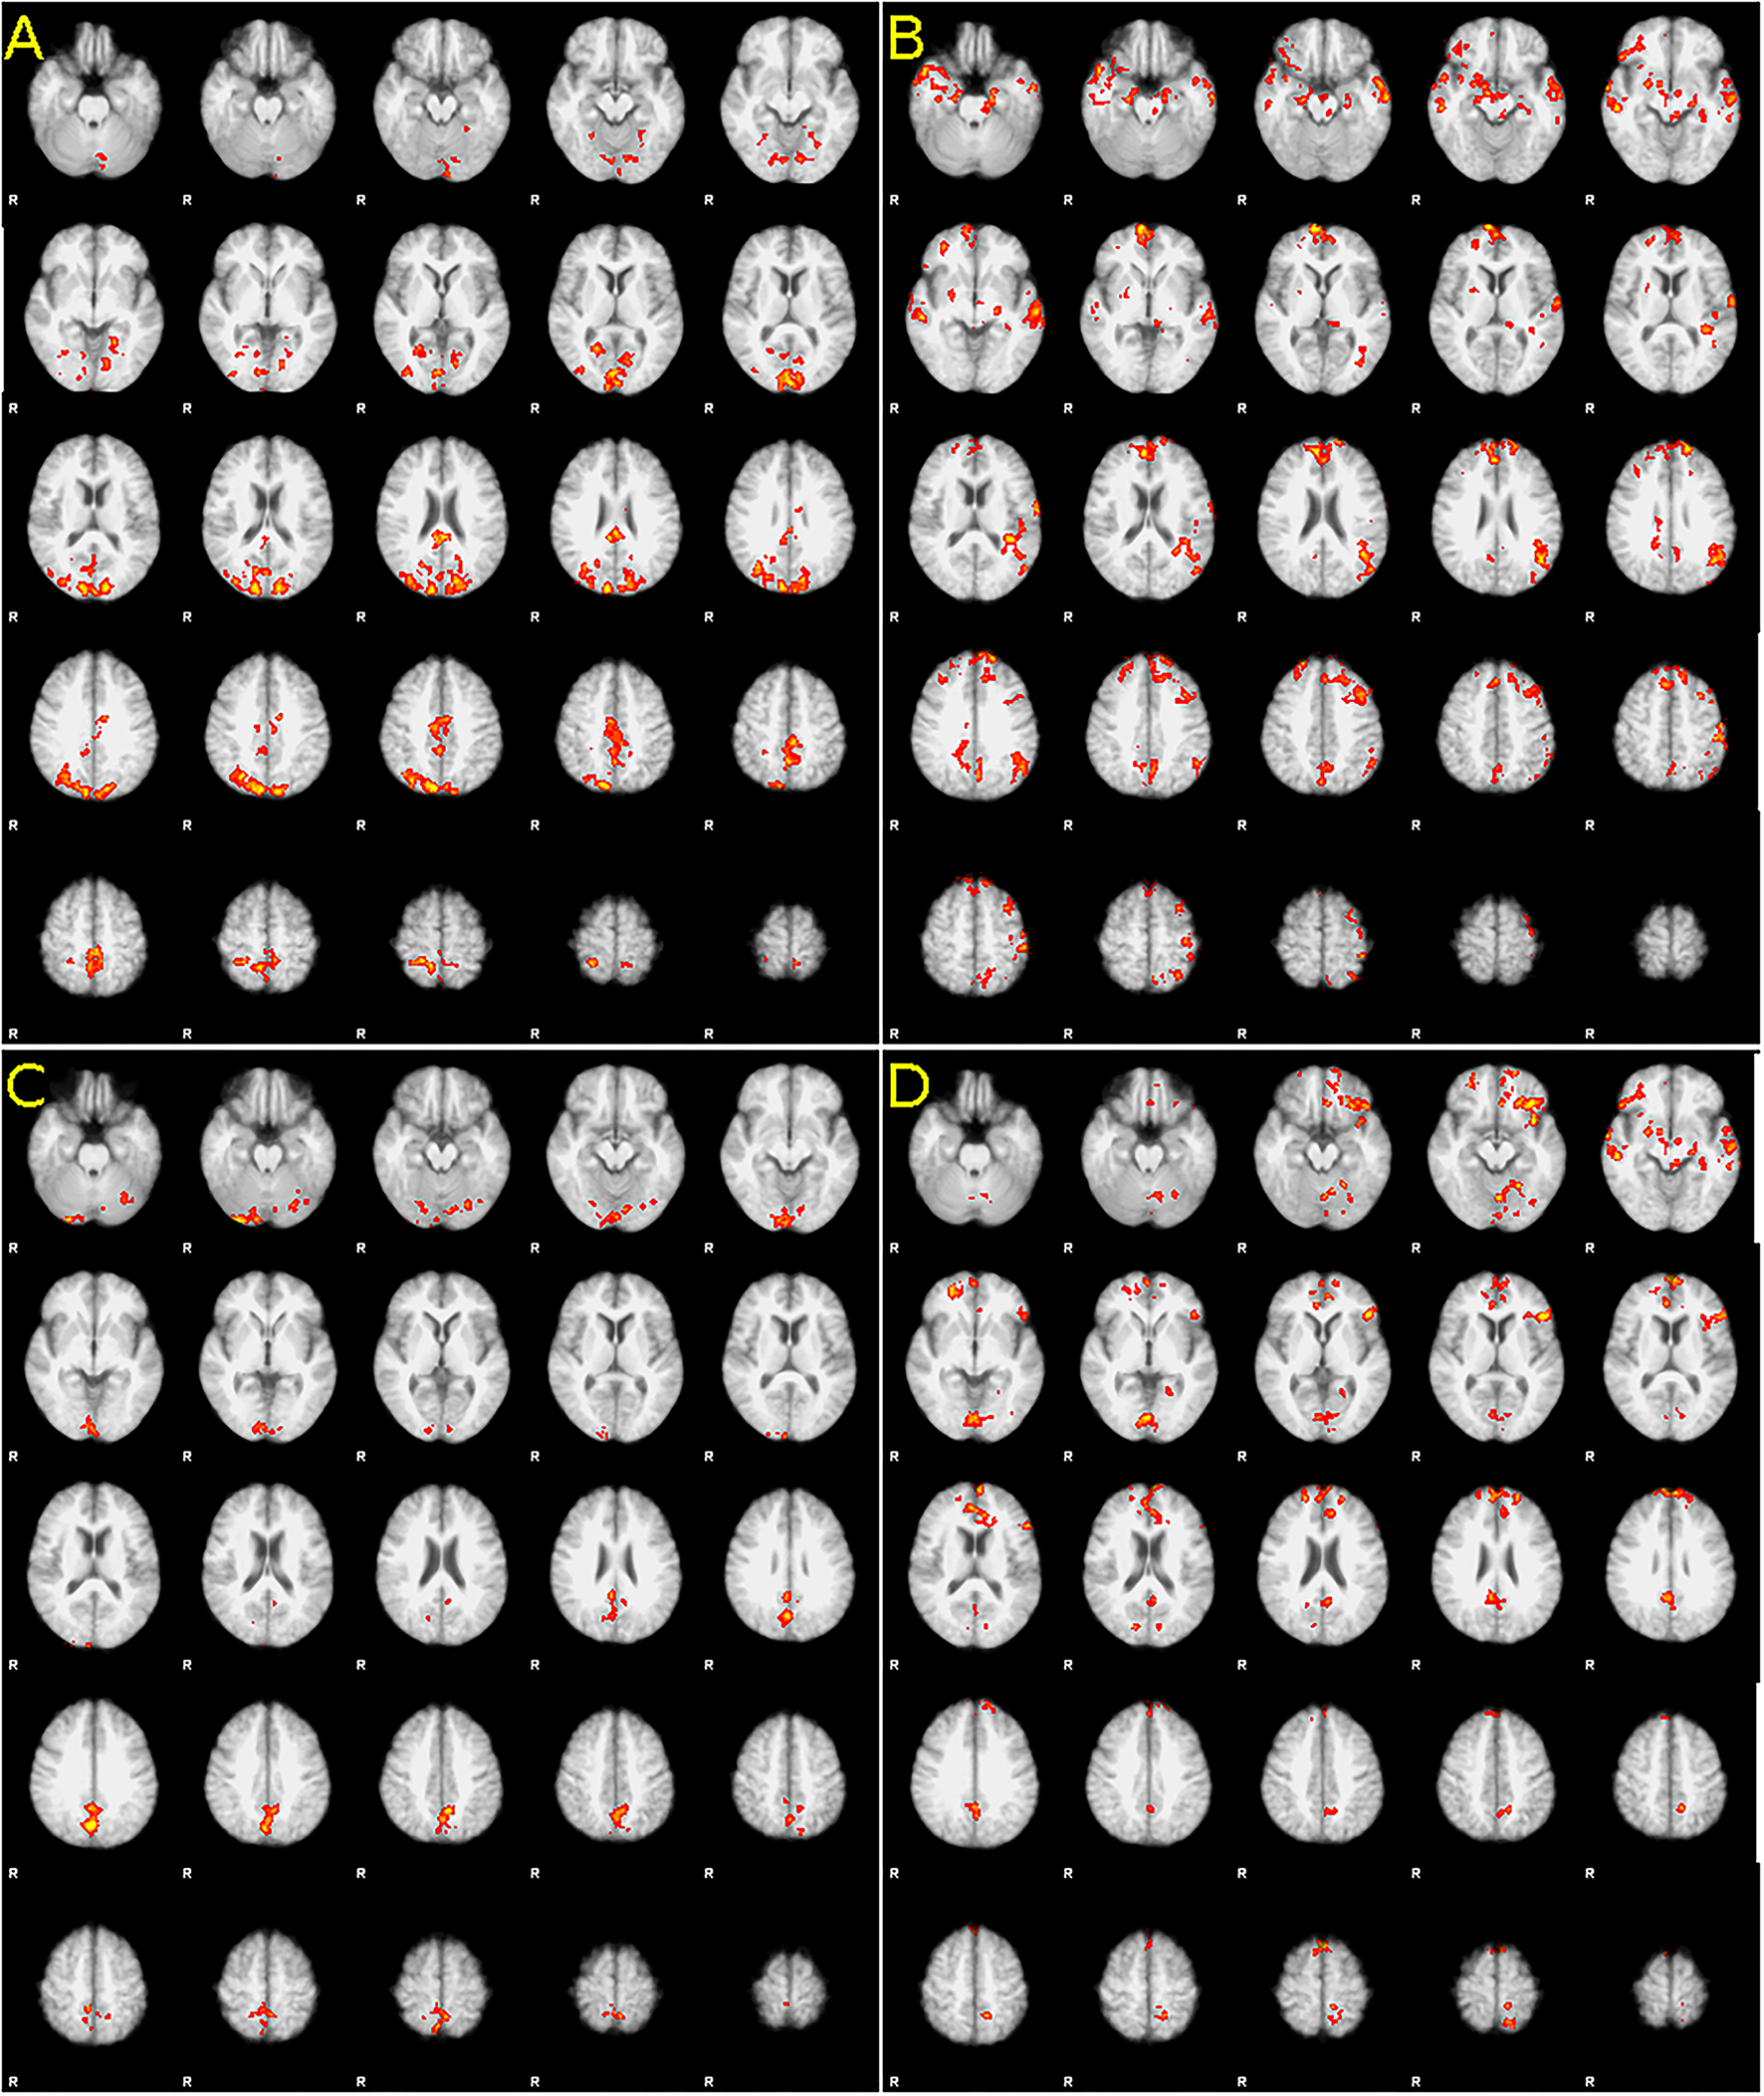

After the first-level statistical analysis (see Methods above), the second-level analysis was performed on the data from both tasks, comparing pairwise baseline to 3 months and 3 months to 12 months: in the mental foot flexion task, an increase in fMRI activation was detected in the comparison between pre-implant and 3 months of follow-up, as well as between 3 and 12 months of examination (Figure 1), predominantly in the bilateral primary motor areas. Between baseline and 3 months, the increase is not only visible in the primary motor area but also in the parietal lobes, sensorimotor area, parts of occipital regions, and in a small cluster in the left cerebellar hemisphere. Between 3 and 12 months, the activation increased again in the primary motor cortex and in the bilateral frontopolar and temporobasal regions.

Figure 1

Difference in activation between [(A,C), left column) baseline and 3 months after baclofen pump implantation, and [(B,D), right column] 3 and 12 months after implantation. Increase in foot in both, (A) baseline and 3 months comparison and (B) 3 and 12 months, (C) Increase in hand in the first 3 months, and decrease (!) (D) between 3 and 12 months. Statistic images were thresholded non-parametrically using clusters determined with Z > 1.6 and a (corrected) cluster significance threshold of P = 0.05. For full statistical output, please see Supplementary Materials.

In the real motor finger tapping task 3 months after pump implantation, an increase in activation was present in the apical part of both cerebellar hemispheres (more on the right) and in the central region (more on the left). Between months 3 and 12, a nearly identical image is seen in an inverted manner: there is a statistically significant decrease in activation (confirmed by testing baseline-12 months with no difference, data not shown). In upper limb, an increase between the baseline and month 3 was detected when MAS was used as a primary measure, including the order of the examination as a confound factor (see Supplementary Material).